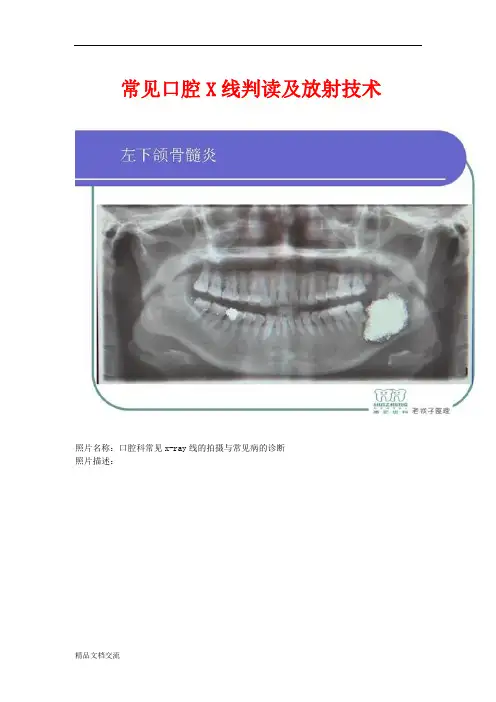

常见口腔X线判读及放射技术

照片名称:口腔科常见x—ray线的拍摄与常见病的诊断

照片描述: